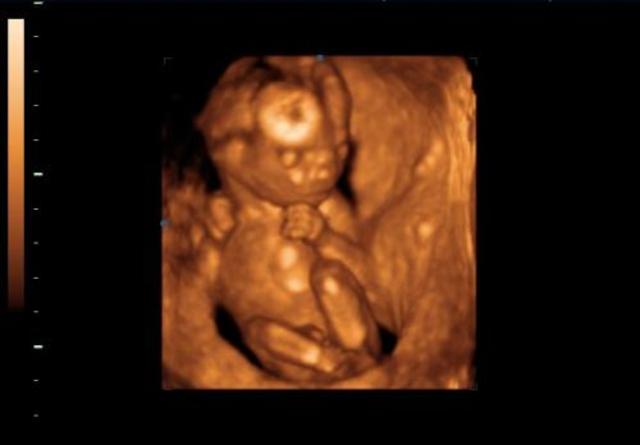

• A magzat fejlődése a harmadik hónapban

A magzat fejlődése a harmadik hónapban

A tizenkettedik hét után már nem embrióról, hanem magzatról beszélünk. A baba ülőmagassága (a fejétől a fenekéig mért érték, CRL) már több mint 4 centiméter, és az arc egyes részei is felismerhetők.